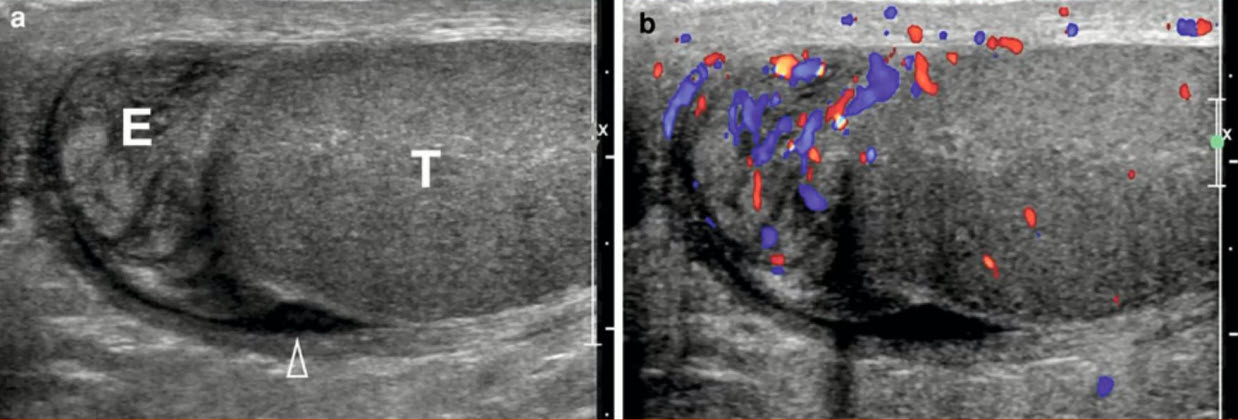

УЗИ диагностика кольцевидной поджелудочной железы: что важно знать